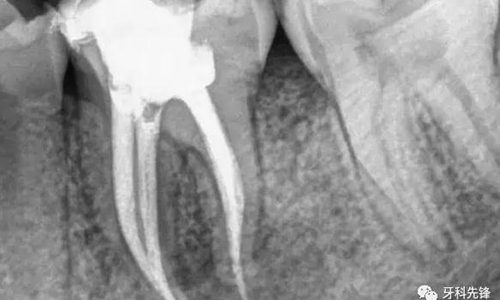

“戴冠”若不夠,樁釘來幫忙

當(dāng)牙齒做完根管治療,由于牙齒自身的結(jié)構(gòu)及治療的需要,牙冠中心一般都是空的,這時,如果直接做牙套,其抗折斷力很差,一般都需要在牙根上打上樁釘,做出個結(jié)實的核,以對抗牙齒使用中的折斷力。

對于后牙來說,做完根管治療之后一定要做上牙冠,否則在承受咬合力量時,牙齒容易出現(xiàn)斷裂。少數(shù)做完根管治療的后牙,若是要做單一的牙冠,只需將所剩牙質(zhì)修補足夠,則可不需做樁釘,但若做完根管治療的后牙是要作為假牙的基牙,則無論牙質(zhì)所剩多少,最后都能做好樁釘。